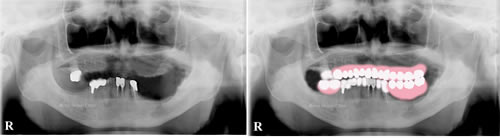

治療後

噛み合わせ治療では患者さんとよくお話しして処置する歯を決定して理想的な噛み合わせになるように治療していきます。画像では最終的にきちんとした義歯が合うように治療できました。